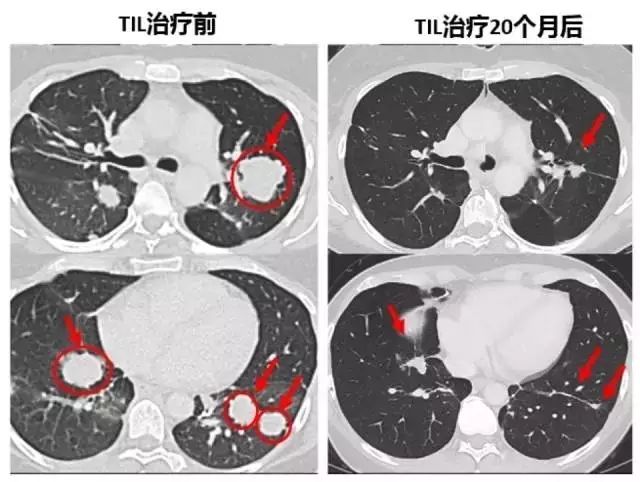

另外一位患者Melinda Bachini,在09年确诊为晚期胆管癌肝转移的患者,术后出现双肺多发转移,她曾尝试过毒副作用很大的化疗方案,头发掉光了,头和脚部的神经严重受损,但是病情没有得到任何控制,甚至恶化了。回输两周之后,困扰了Melinda很久的慢性咳嗽开始缓解了。第二次回输后,效果真的惊人!她全身肿瘤开始迅速缩小,体力恢复很快。治疗后仅仅一个月,她已经和家人去高山滑雪了!